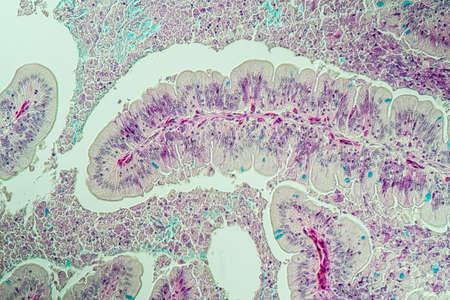

Cross section of intestinal glands (crypts of Lieberkühn) showing mucous goblet cells. Human colon.

Histopathology of intestinal adenoma, light micrograph, photo under microscope

Histopathology of cholera under microscope view for education.